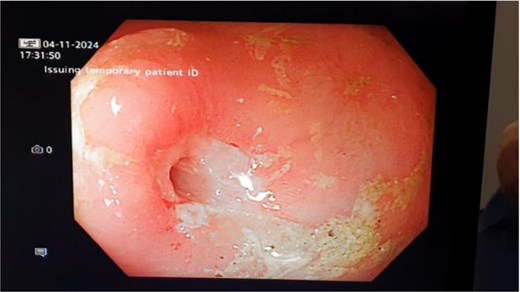

Eight months later she presented to the emergency department with symptoms of SBO. A balloon dilatation of 3 strictures in the obstructing segment was performed (Fig. 2).